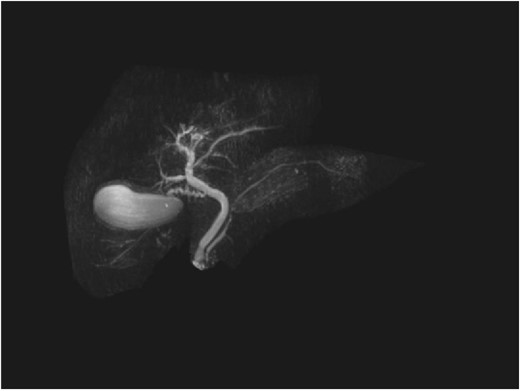

Repeat liver function test 1 month later showed dramatic improvement, with bilirubin level at 25 umol/L (normal 2–20), total IgG 13.23 g/L (normal 6.5–15.2), IgG4 1.45 g/L (normal 0.04–0.86), and CA19-9 44 (normal < 34). The steroids were gradually tapered and ceased. Repeat MRI 4 months later showed a normal biliary system with complete resolution of the common bile duct pathology (Fig. 4).